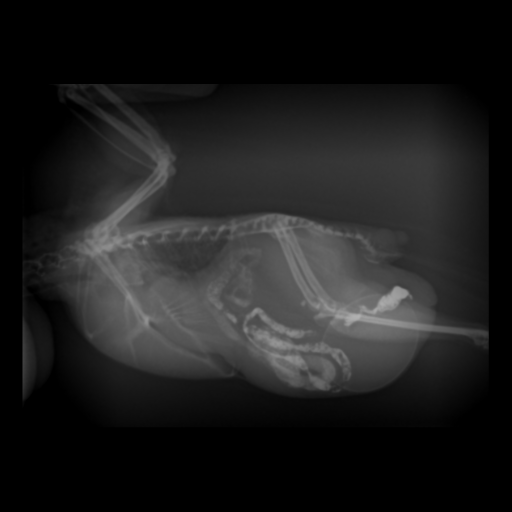

レントゲンを撮影したところ腹部下方に卵が確認できました。さらに卵巣や卵管の領域の陰影が拡大しており、筋胃が下方に押されている所見もあったため、超音波検査も実施しました。

手術はまず皮膚、腹筋、肝後中隔の順に切開し、一番手前にある卵の摘出から始めました。腹腔内を確認すると卵は卵管内にあることと、卵材か卵か疑われたところには殻の薄い軟卵があることがわかりました。よって2卵塞であることが判明しました。